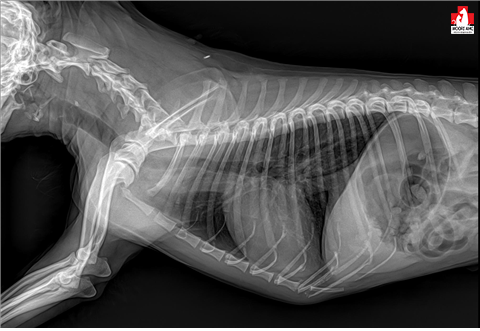

일단 엑스레이를 찍었고요.

사진처럼 튀어나와 있어 보여요

다행히 흉부 방사선상의 특이소견은 없었습니다